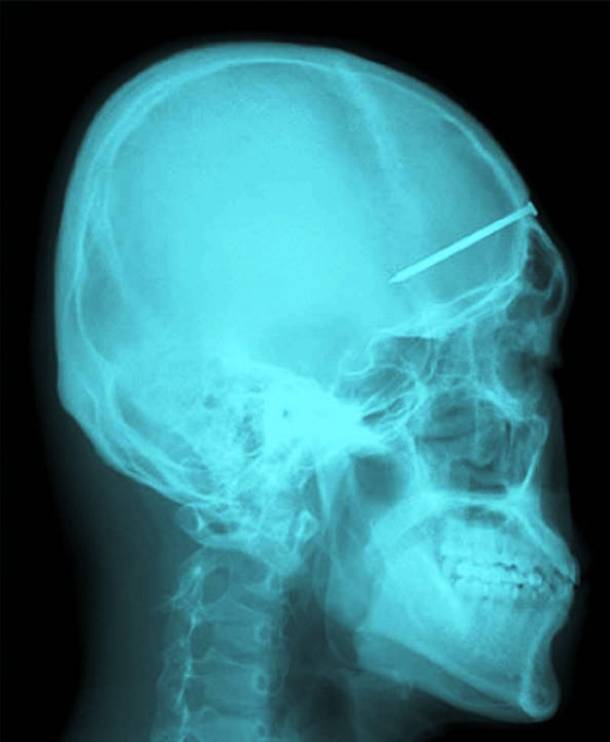

2. A Nail From Mouth To Brain

This man, named Patrick Lawler went to the dentist complaining of toothache. What the dentist found when he performed an X Ray was a nail which started in the roof of his mouth and reached all the way into his brain. There was no explanation as to how it had arrived there...Advertisement